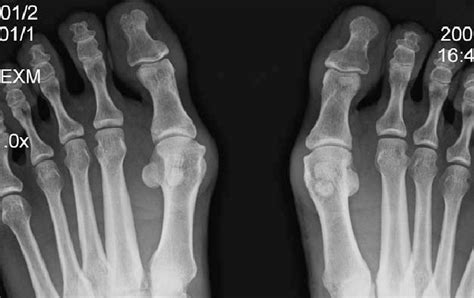

Fractures can occur when a person falls and lands bluntly on the ball of the foot. This topic review will discuss sesamoid fractures of the foot in adults.

Acta scientific orthopaedics 3.3 (2020). Sesamoid fractures most commonly refer to the bones located under the big toe. Sesamoid bones are found embedded in the tendons near many joints.

Rest, ice, and elevate your foot. Turf toe is a hyperextension of the big toe joint in an upward direction. These foot bones are located underneath the foot, one on the outer side of the foot and the other near the middle of the the sesamoid bones are subject to breakage (fracture) as well as sesamoiditis. Sesamoid fracture and injuries treated by top foot surgeons in baltimore. Fracture of the medial sesamoid with slight edema (white arrow). Sesamoid fractures occur as a result of trauma to a previous unipartite sesamoid bone. 301 moved permanently these pictures of this page are about:sesamoid bone foot fracture. What is a sesamoid fracture? Often sesamoid fractures are described as turf toe. Sesamoid partition is a common normal variant. Sesamoiditis occurs on the bottom of the foot, just behind the big toe. Stress fractures of the sesamoid bones can also cause sesamoiditis. There are normally two sesamoid bones on each foot; The sesamoids are two bones underneath the great toe. These are the least common fractures of the forefoot. Four weeks ago i dropped a heavy object on my right foot. Although sesamoiditis used to be a rare cause of foot pain and disability, it has become more common in recent years, and it is.